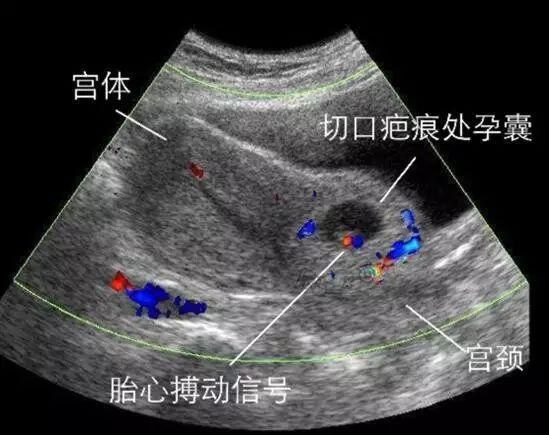

因为之前剖宫产的原因,蒋红除了肚子上有一条疤痕,在看不到的子宫上同样也有一条永久性疤痕。当再次怀孕时,若胚胎是在子宫瘢痕处着床,不在正常的子宫内,就会像一颗种子随着时间在这条缝隙中生长,很容易通过裂隙把肌肉撕开,从而导致子宫破裂和大出血,不仅胎儿的成活率为零,孕妇也会有生命危险。这种现象在医学上称为“子宫瘢痕妊娠”,是一种凶险性不亚于宫外孕的产科急症。

◎ B超显示的子宫瘢痕妊娠。/ 网络图片

而通过检查发现,蒋红正是子宫瘢痕妊娠的情况,为了她的生命安全,医生建议她最好尽快终止妊娠。但对于好不容易盼来二胎的蒋红来说,现在要她把自己的孩子流掉,她的内心是痛苦和不舍的,“早知道我当初就顺产了,我是可以顺产的……”